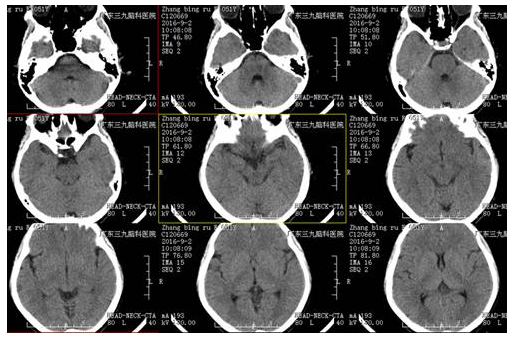

术中▲

手术由神经外一科主任张良博士主刀完成,完善术前检查后,在全麻下行“右侧后交通动脉瘤夹闭术”,经系统治疗后患者颞部疼痛及眼睑下垂症状较前缓解康复出院。